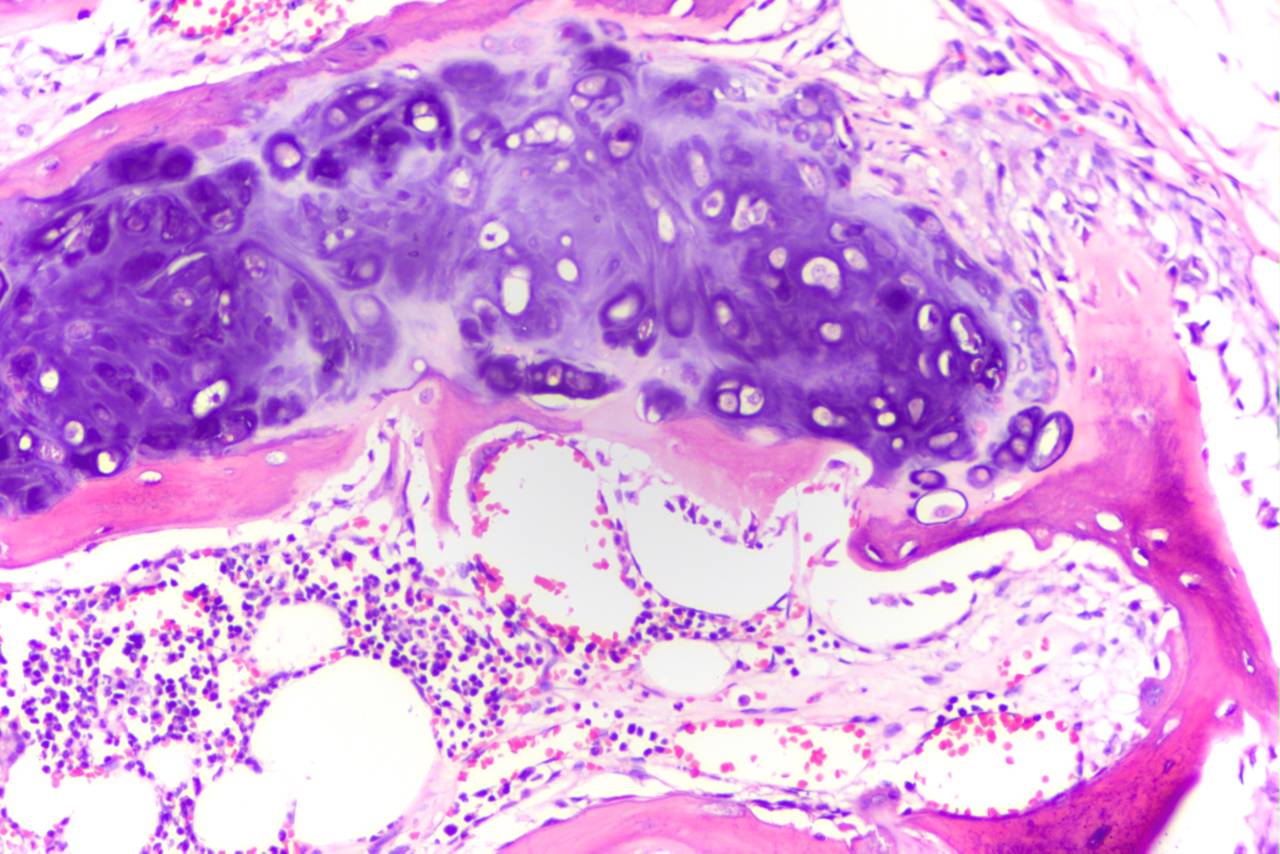

H&E: Hematoxilina e Eosina

Diferência estruturas basofílicas e acidofílicas, hematoxilina e eosina respectivamente. Cora núcleos, reticulo endoplasmático rugoso e ácidos nucleicos em roxo pela hematoxilina e citoplasma, fibras colágenas entre outras estruturas acidofílicas em rosa pela eosina.